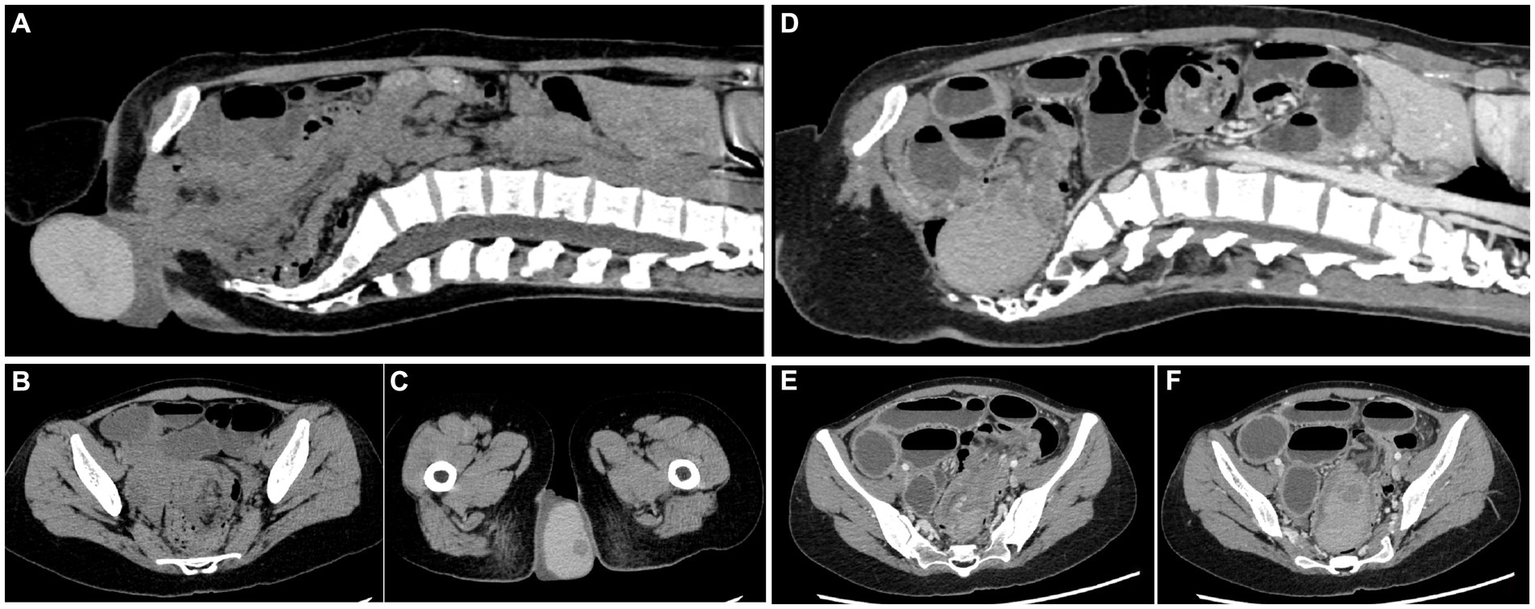

Upon admission, an abdomen and pelvis computed tomography (CT) scan indicated an intestinal structure disorder combined with incomplete intestinal obstruction, suspicious intussusception, and partial intestinal duct prolapse through the anus. An external anal mass high-density shadow (CT value ≈ 90) of size ≈ 78*61*41 mm and nature unknown was identified (Figures 1A–C). Based on these findings, the root of the mass was anticipated to be at least above the junction of the rectosigmoid colon.

Figure 1. Computed tomography of the abdomen and pelvis. (A–C) Plain CT before the return of the cyst. (D–F) Enhanced CT after the return of the cyst. The intestinal duct structure is disordered, and the small intestine is obviously dilated.

To further determine the nature of the mass and its relationship with the intestine, a colonoscopy was performed 2 days later. The patient was orally prepared with polyethylene glycol electrolyte powder 42 h after the mass was restored (8). Within 3 h, the intake was approximately 1,300 mL and the vomiting was approximately 500 mL, largely including polyethylene glycol electrolyte powder liquid containing gastric juice. After the mass had returned for 54 h (48 h + 6 h), the patient underwent a colonoscopy under intravenous anesthesia. Screening revealed a large smooth-surfaced mucosal mass in the rectum. The mass had extended into the descending colon, which contained a large amount of feces that could not be passed. Intussusception was considered highly probable. After communication with the patient and her family members, the patient underwent an enhanced abdominal CT. A pelvic cystic mass with clear boundaries and thicker, uniform internal density was identified. There was no enhancement in the cyst, but obvious enhancement in the cyst wall that was consistent with that of the surrounding intestinal duct. The findings indicated that the ileocolecular intussusception was associated with a low-level intestinal obstruction that had become aggravated since the patient’s initial hospitalization on 16 September. A large, dense mass at the distal end of the intussusception was located in the pelvic cavity, and a cystic lesion was considered (Figure 1).

A Japanese study on the elective laparoscopic investigation of patients with intussusception found that the mean age of patients was 69 (29–100) years, and the incidence due to cecal site tumors was 42.8%. One 93-year-old woman (BMI = 15.1) underwent laparoscopic exploration surgery following abdominal pain. During the operation, it was confirmed that cecal cancer had entered the colon, causing pain from splenic flexure of colon intussusception (2). In the current case study, a CT scan showed intussusception, and the ileocecal region was unclear (Figures 1, 2), suggesting that the mass had originated in this area. The absence of preoperative cancer markers and the imaging characteristics of the mass also suggested that it was more likely to be benign. Intraoperative findings from the current case study and prior study results indicate that an abnormal mesangium and ligaments in the ileocecal region and abnormal growth of an ileocecal mass are high-risk factors for intussusception. Thus, in cases of unexplained intussusception, the possibility that the tumor originated from the ileocecal region should be considered.